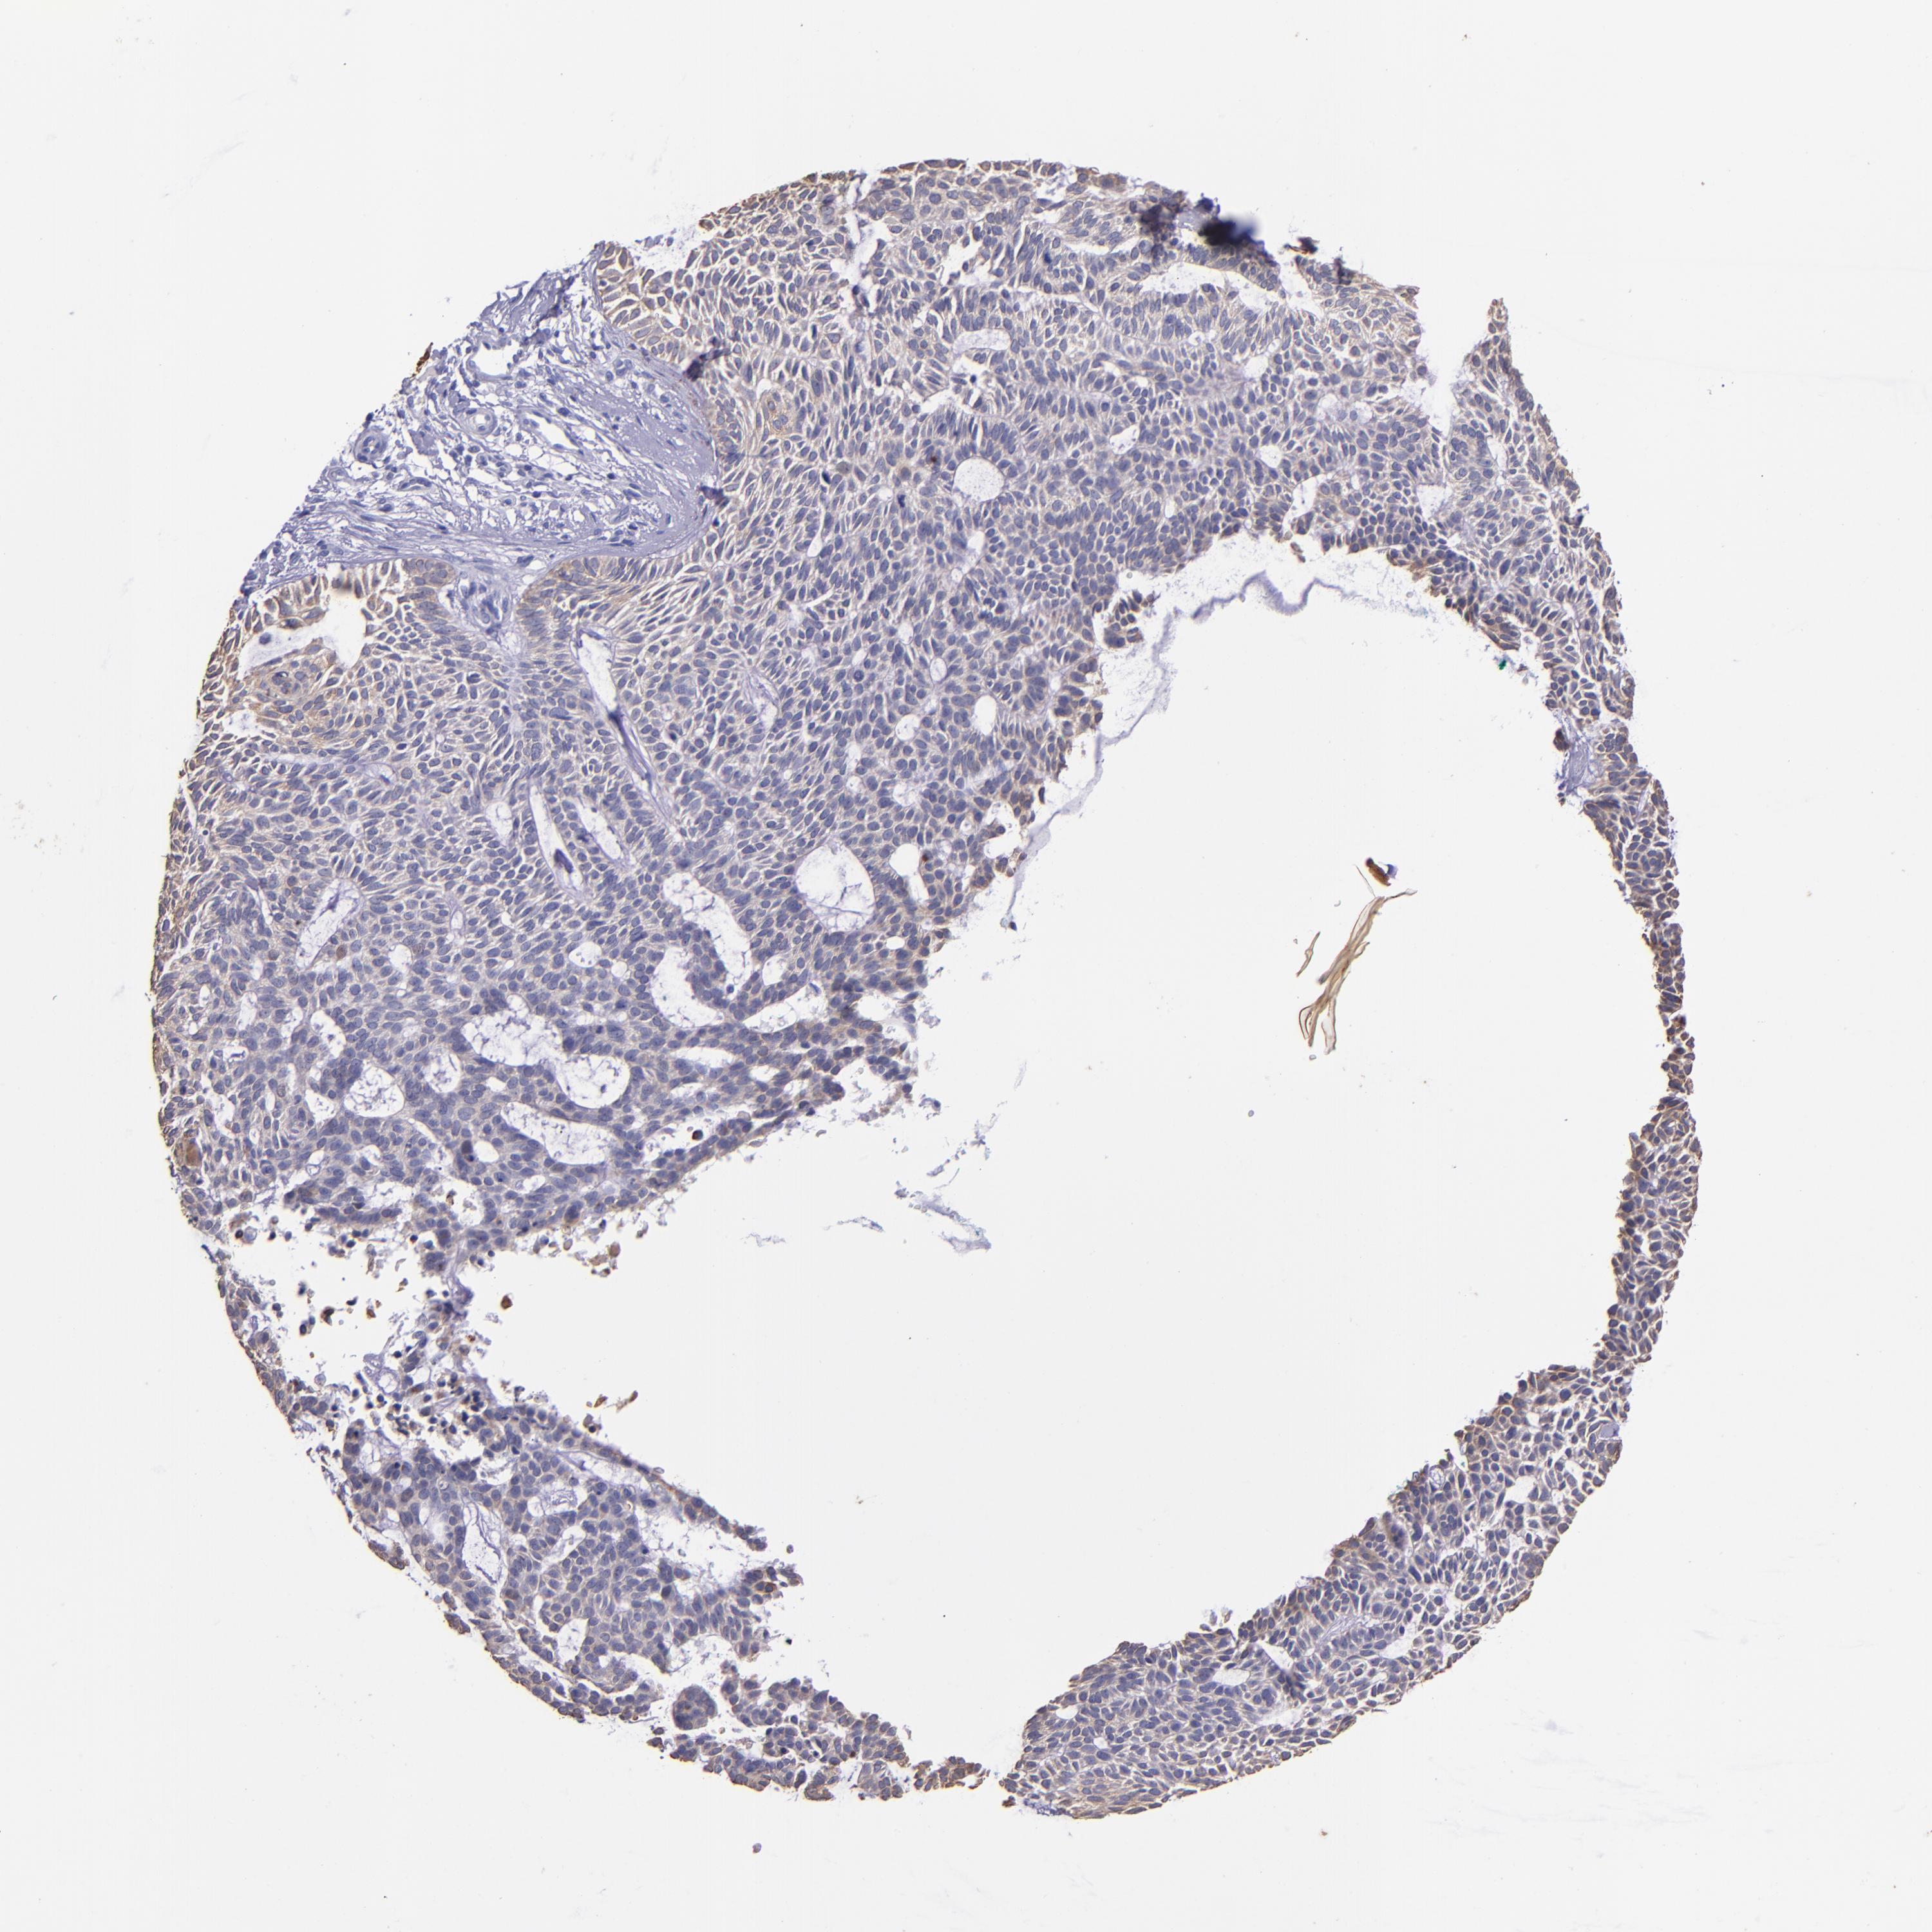

SKIN CANCER - Protein expressioni

A mouse-over function shows sample information and annotation data. Click on an image to view it in a full screen mode. Samples can be filtered based on level of antibody staining by selecting one or several of the following categories: high, medium, low and not detected. The assay and annotation is described here.

Antibody staining in the annotated cell types in the current human tissue is reported as not detected, low, medium, or high, based on conventional immunohistochemistry profiling in selected tissues. This score is based on the combination of the staining intensity and fraction of stained cells.

Each image is clickable and will lead to virtual microscopy that enables deeper exploration of all samples and also displays staining intensity scores, fraction scores and subcellular localization as well as patient and tissue information for each sample.

Antibody HPA034881

Antibody CAB002154

Basal cell carcinoma

Squamous cell carcinoma, NOS